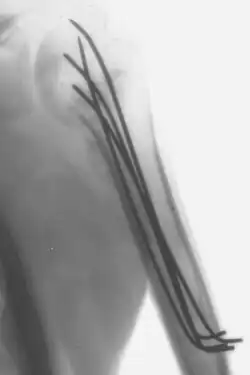

- L'enclouage : On enfonce une tige de morphologie adaptée dans le canal central d'un os long (le tibia par exemple). En formant un pas de vis, l'enclouage avec alésage peut même parfois éviter des rotations dans le foyer de fracture.